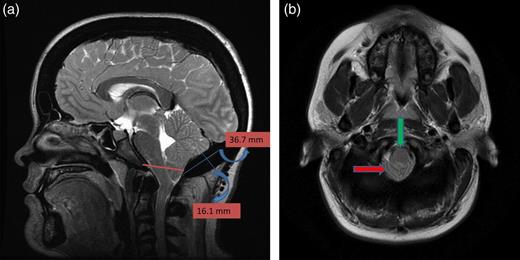

A 25-year-old female patient presented with 1-year history of occipital headache. The headache was increasing with coughing, sneezing and bending over. She had also complaints of intermittent bilateral hand numbness and bilateral feet burning. She was evaluated with magnetic resonance imaging (MRI), which showed Chiari I malformation with a 7 mm descent of cerebellar tonsils (Fig. 1 a and b). Computed tomography demonstrated diffuse calvarial thickening and loss of the medullary space (Fig. 2). Her past medical history was consistent with left eye surgery due to amblyopia when she was a child and she was blind in her left eye. Radioactive 131I treatment had been given due to the Graves’ disease and hyperthyroidism; therefore, she was hypothyroidic and was using levothyroxine daily. Her mother also was operated on because of the Chiari malformation. She had four siblings, and they did not have any pertinent medical history. Her physical examination revealed prominent occipital area and midfacial hypoplasia. Increased cortical thickness in her long bones was also demonstrated (Fig. 3 a–c). There were no abnormal findings on neurological examination except of left eye amorozis. The patient underwent surgery for decompression of posterior fossa. Large enough posterior fossa craniectomy with C1 laminectomy was performed with SSEP and MEP monitoring. Dura was opened in ‘Y’ shape, and duraplasty was performed with the pericranium. Arachnoid was kept intact. Her headaches improved significantly in postoperative period. She developed superficial wound infection, which was treated with simple washout and antibiotics.

Axial CT image (bone window) showing diffuse calvarial thickening and loss of the medullary space.